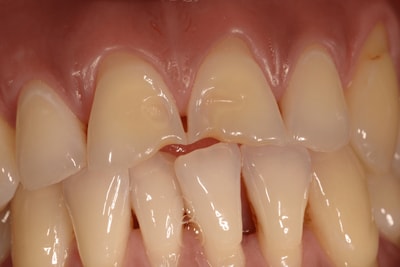

Les composites stratifiés

Lorsqu’un délabrement survient sur une dent antérieure (visible, où l’esthétique est une priorité), et que l’indication n’est ni une facette, ni une couronne, nous vous proposons de réaliser une restauration par un composite stratifié. Il s’agit de reconstituer la partie manquante de la dent, en respectant les différentes entités de la dent. Nous monterons différentes masses de dentine, d’émail, les particularités de la dent, en respectant la carte d’identité de la dent (établie selon une analyse et des relevés morphologique de la dent, cartographique de la couleur, cartographique de l’émail et de la dentine, topographique (état de surface)).

Les taches de l'émail

De nos jours, nous sommes de plus en plus confrontés à des tâches disgracieuses siégeant sur les dents antérieures. Les causes sont multiples. Que ce soient des fluoroses, des tâches blanches de l’émail, des tâches marrons , noires ou vertes, il faut savoir proposer, à notre patientèle, une solution simple et pérenne. En tenant compte des dernières évolutions scientifiques et industrielles, nous avons élaboré un protocole spécifique à chaque cas.